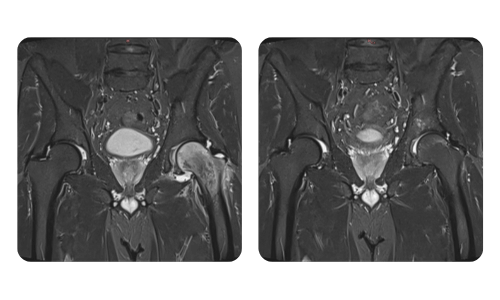

Progresul pacienților noștri, măsurat înainte și după terapia hiperbară, reflectă eficiența și impactul pozitiv al tratamentului. Descoperă rezultate documentate ale terapiei hiperbare la clinica Hyperbarium Oradea, bazate pe evaluări clinice și date obiective care evidențiază îmbunătățiri semnificative în diverse afecțiuni.